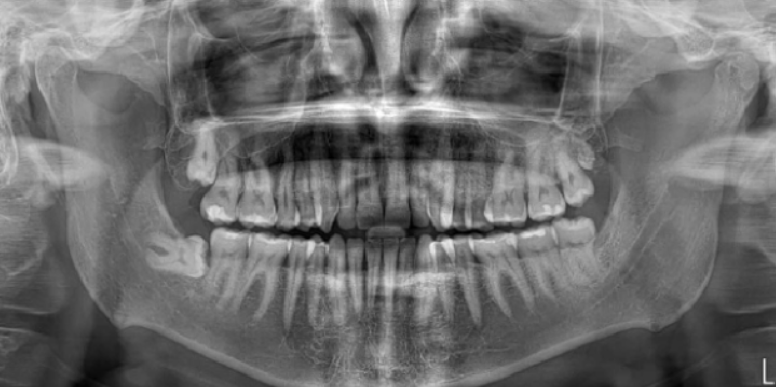

- Initial Examination and Imaging: We perform a thorough oral exam and use advanced imaging, like Cone Beam 3D scans, to assess tooth position and plan the extraction.

At South Florida Institute of Oral Surgery, we use the latest dental technology to ensure safe and precise wisdom teeth removal. Our advanced tools, including digital X-rays and Cone Beam 3D imaging, allow our oral surgeons to evaluate tooth position, root structure, and surrounding bone with exceptional accuracy. This technology helps us minimize discomfort and reduce recovery time for patients undergoing wisdom teeth extractions in Coral Springs & Pompano Beach. By combining innovation with quality care, we provide a stress-free experience and promote optimal oral health for every patient.